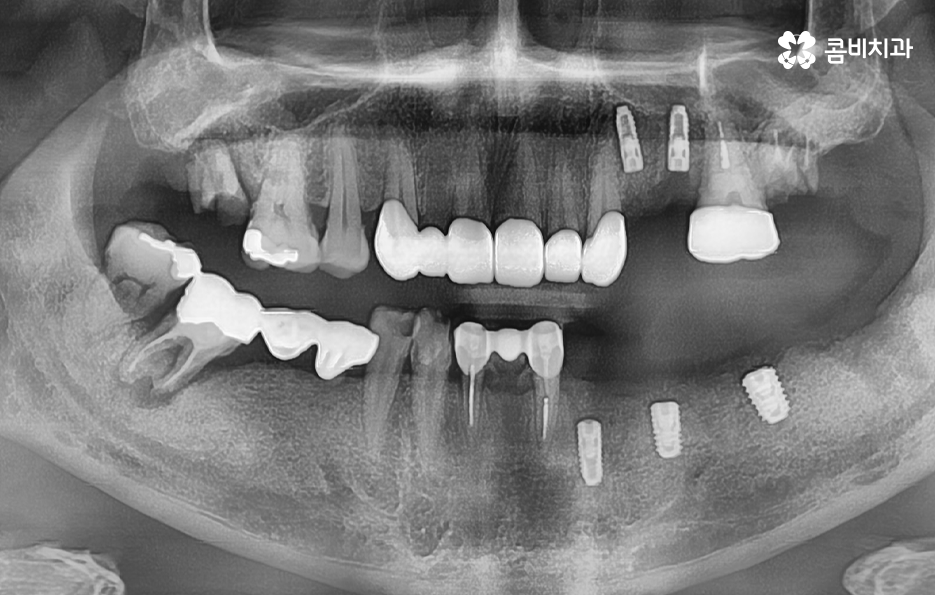

임플란트 치조골 어떻게 뼈이식을 하면 될까요

앞서 설명드린 이유로 잇몸 뼈의 상태가 부족하신 분들의 경우에는 뼈이식을 추가적으로 진행하여 자신의 뼈처럼 단단하게 굳게 되면 일반적으로 건강한 잇몸 뼈를 가진 분들과 거의 동일하게 임플란트 수명이 유지된다고 보면 될 거예요

임플란트 시술 전과 후에는 모두 임플란트 치조골 상태의 중요성이 무척이나 크며 시술의 성공률에도 크게 중요하며 시술 후 수명 유지를 좌우할 정도 임플란트 치료에 있어서 치조골의 상태는 무척이나 중요하다고 이해하시면 좋을 거예요